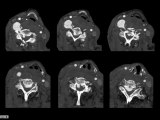

Flexion de C1 pendant rotation RCS

Cette vidéo représente la flexion en 2 temps de l'atlas au cours d'une rotation du rachis cervical supérieur.